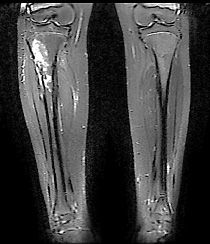

Klasik osteosarkom uzun kemiklerde kötü sınırlı, kemik yıkımına neden olan litik/sklerotik görünümlü lezyonlardır. Periostta kemiğe dik açıda oluşan kemik oluşumu (batan güneş manzarası) patogonomiktir. Yumuşak doku komponenti eşlik eder. BT kemik içerisindeki patolojileri göstermede yeterlidir. MRI ise yumuşak doku yayılımını, damar ve sinirin tutulup tutulmadığını, fiz hattının (büyüme kıkırdağı) etkilenip etkilenmediğini, komşu eklemin tutulup tutulmadığını, skip metastazların olup olmadığını ve uygun biyopsi yerinin belirlenmesinde yardımcıdır.

Radyolojik incelemede permeatif ve infiltratif kemik destüksiyonu vardır. Diafizde soğan halkaları tarzında periost reaksiyonu görülür. MRI incelemesinde yumuşak doku komponenti ve içerisinde nekroz alanlarının olup olmadığı, lezyonun kemik içerisine yayılımı, skip metastazlarının olup olmadığı, eklem ve komşu damar ve sinirlerin etkilenip etkilenmediği değerlendirilir. Kemik sintigrafisi tümörün aktivitesi ve metastazların varlığının değerlendirilmesi için kullanılır. Kesin tanı biyopsi ile konur.